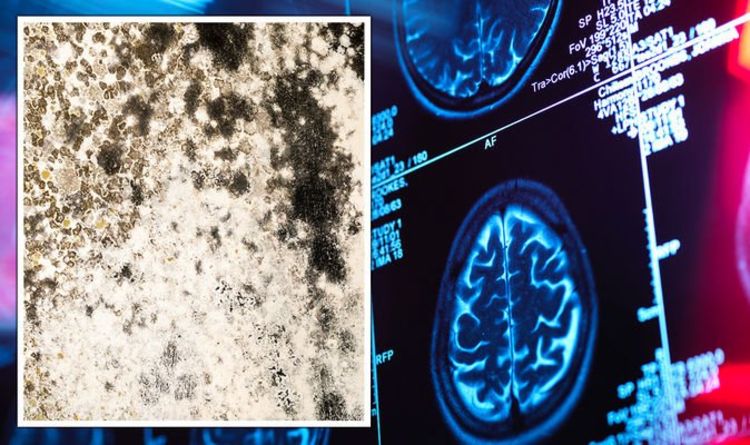

Bác sĩ sốc khi phát hiện ra nấm đen trong não người đàn ông, không tin được rằng bệnh nhân còn sống. Các bác sĩ không thể tin được khi phát hiện một người đàn ông bị nấm mốc đen mọc trên não.

Căn bệnh này hiếm gặp và có tỷ lệ tử vong vô cùng cao. Ảnh: Getty

Quá trình quét MRI cho thấy một điểm bất thường hình chữ O trên não của Bottenus. Sau tám tháng kiểm tra bằng MRI, sinh thiết và thậm chí cả vòi tủy sống, các bác sĩ đã phát hiện ra căn nguyên của bệnh, đó chính là một ổ áp xe có nấm mốc đen đang phát triển trên não của ông.